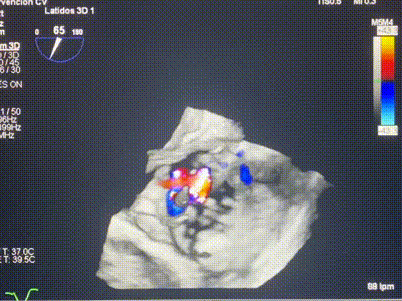

術(shù)中輸送器在超聲引導下調(diào)整位置

手術(shù)在全麻狀態(tài)下進行。術(shù)者采用經(jīng)右側(cè)頸靜脈入路的方式將輸送器送入患者心臟內(nèi),在TEE及DSA引導下調(diào)整輸送器頭端角度,使得輸送器與三尖瓣瓣環(huán)平面垂直。在輸送器進入右心室后釋放室間隔錨定裝置,而后釋放瓣葉夾持件(2個耳片結(jié)構(gòu))成垂直狀態(tài)。在TEE及DSA確定夾持件固定至三尖瓣葉根部且位于右室側(cè)后釋放人工瓣心房側(cè)盤片。隨后調(diào)整瓣膜同軸性以及室間隔錨定件位置(貼合室間隔),前推藏針管并固定,進而釋放室間隔錨定裝置,并再次確認瓣膜位置、穩(wěn)定性及同軸性,合攏輸送鞘后撤出輸送器,完成LuX-Valve Plus人工三尖瓣瓣膜的植入,僅殘余微量瓣周漏。且經(jīng)手術(shù)中心電生理團隊評估,病人的起搏器和ICD功能沒有受到影響。